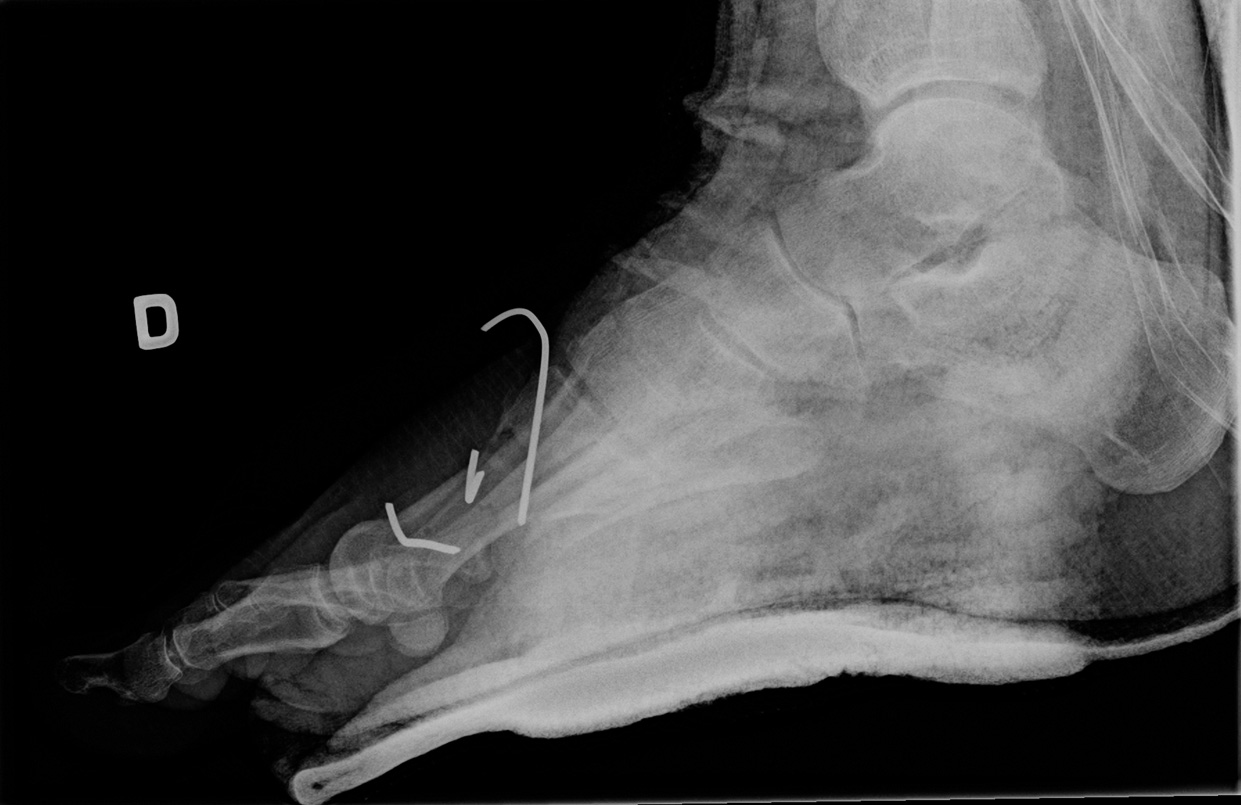

54-year-old male:

Postoperative control of a first metatarsal bone fracture.

A proximal wire was inserted longitudinaly to fix the base and distal fragments.

1st metatarsal alignment

Postoperative alignment is adequate.